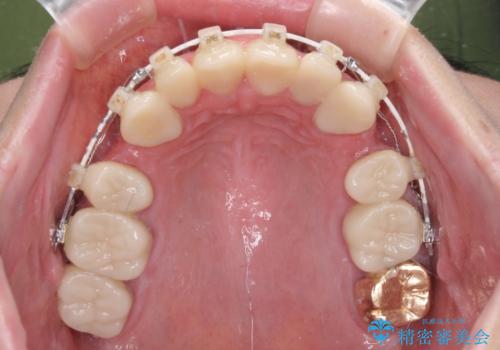

当初はほとんどの歯をむし歯治療のようにオールセラミッククラウンにて補綴治療を行う予定でしたが、仮歯に置き換えた時点で、口元の突出感や下顎前歯の叢生が気になるとのことで、上下左右の第一小臼歯4本を抜歯したワイヤー装置での抜歯矯正を行うこととしました。

矯正治療終了後に、残った歯をオールセラミッククラウンにて補綴治療を行うこととしました。